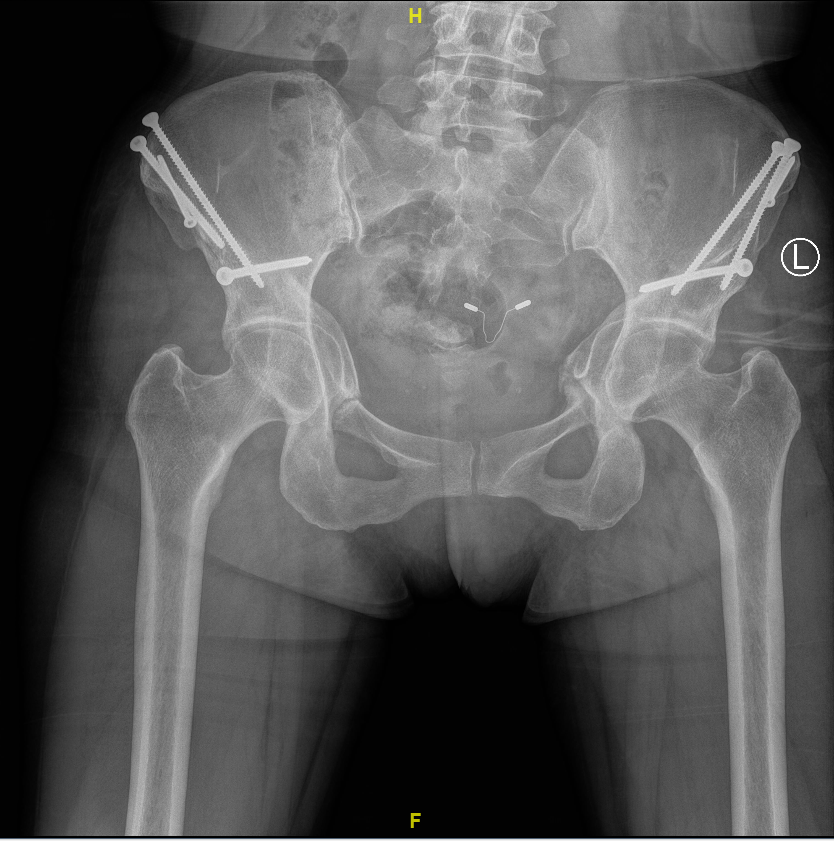

2021-01 左侧髋臼PAO截骨术后1年3月,右侧术后2年3个月:双髋关节正位X线片

2021-07 左侧髋臼和股骨近端上下PAO截骨术后1.5年:双髋关节正位X线片